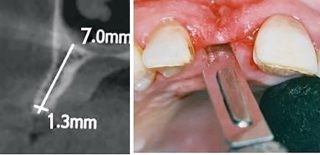

This is performed by separating the buccal cortical aspect of bone from its lingual or palatal counterparts (Fig.2) which leads to create bone sockets in the correct position with desirable relationship, harmony and aesthetics.

OM Sinus lift; resulting in Dome created by Osseo-Manipulation along with compaction, condensation and lift

Voids around the implant and the bone lead to resorption if the gap is large and the tissue biotype is thin; the use of bone grafts in the aesthetic zone and in the posterior areas manipulate the bone by gentle

maneuvering or compaction of bone with bone molders or gently tapping the bone with chisels towards the implant. This technique may not only close the voids but also will significantly enhance the densification of bone and increases the primary stability of the implant.

The implant should be, all around the interradicular bone. Spontaneous healing & osseointegration is more favorable if the Implants placed have a Jumping gap –G, [18] of less than 2mm 7. If the gap between the implant and the bone is more than 2 mm then the author strongly recommends using platelet-rich fibrin, barrier membrane, or bone grafts to facilitate bone formation and obliterate the epithelial ingrowth.